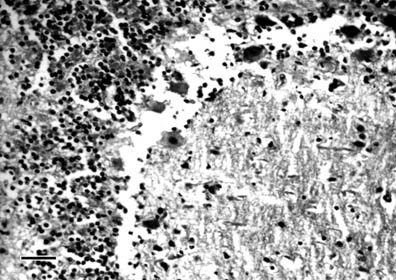

A diffuse granular and lipid degeneration (proved by Sudan III staining of frozen sections) was established in the liver. Small necroses were occasionally observed in some regions, predominantly in sheep of group II in later stages (on the 16th and 30th days of the experiment). Sinusoidal capillaries were hyperaemic and Disse's spaces were enlarged with pericapillar oedema. The activated Kupffer cells were often observed in the lumen of capillaries (Fig. 3).

Fig. 3. Photomicrograph of liver of sheep in group II. Group II was treated

per os with 6×7.0 mg of mercury in 1% mercuric chloride solution, biopsed

using laparotomy on the 10th day of the experiment. Granular and lipid

degeneration in hepatocytes. Enlargement of Disse's pericapillar spaces.

Activated Kupffer cells in the lumen of capillaries.

H/E; 400 ×; bar = 25 µm.